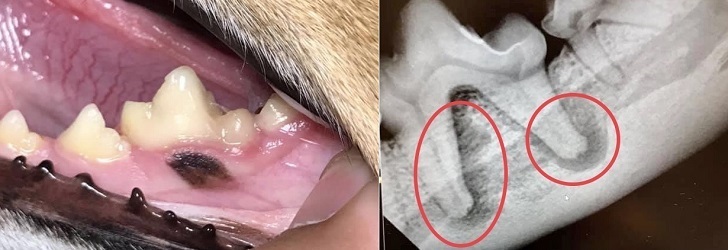

Did you know that Mira Mar Vets has the most advance dental equipment in the Great Southern region?  We have a full dental x-ray suite, and a full mouth dental x-ray profile is provided as part of the service for ALL animals undergoing a dental procedure.  This means we have accurate information about the state of your pet’s tooth roots - so that all diseased teeth can be identified and also ensuring that no teeth are extracted unnecessarily.  A lot of dental disease occurs BELOW the gumline, as the image below shows, so dental x-rays are the gold standard to detect disease before it is obvious externally.